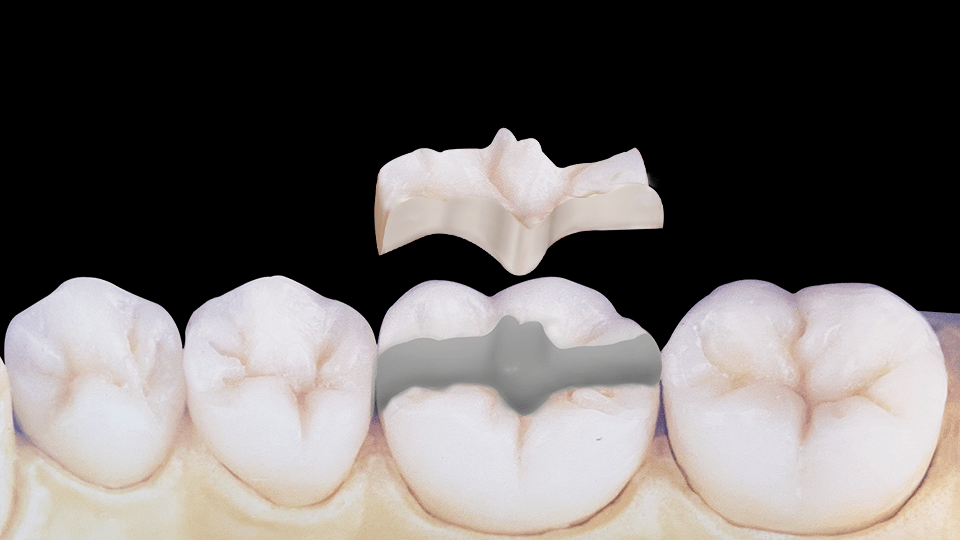

INCRUSTACIÓN

Restauración fija rígida de cerámica o de resina reforzada con cerámica que reemplaza la porción de la pieza dentaria perdida. Se realiza de manera indirecta, es decir por fuera de la cavidad bucal.

Se indican cuando la pérdida de remanente dentario sea mayor y por ende se dificulte devolver la morfología perdida con una restauración directa.